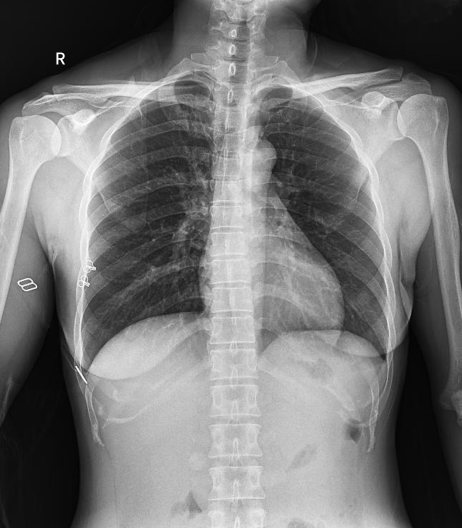

普利德醫(yī)療自主研發(fā)的新一代數(shù)字化X線透視攝影系統(tǒng),可應用于DR攝影、數(shù)字透視、數(shù)字造影以及可視化精準DR拍片等多種臨床X線檢查領域。

球管傾斜攝影角度-45°~45°,滿足臨床各部位各角度的攝影需求。如:髕骨軸位、頸椎正位、骶尾椎、鼻竇瓦氏位、梅氏位等部位檢查。

拉伸自如:SID電動拉伸,最長可延伸至1.8米,滿足放射科室各種拍片距離的需求。如:GBZ 70-2015職業(yè)性塵肺病的診斷標準中對胸片拍片距離1.8米的要求。